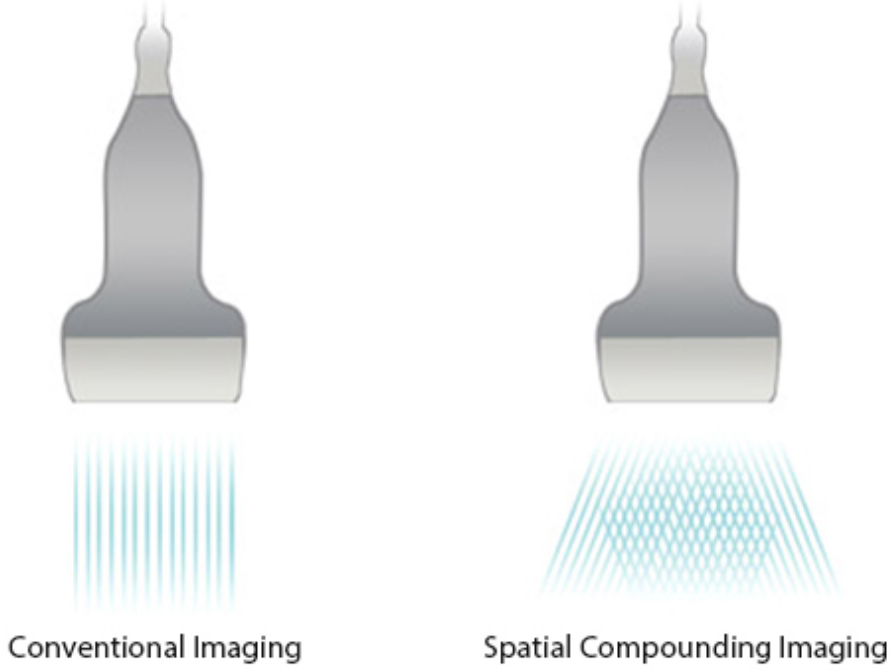

iBeam?

Memungkinkan penggunaan beberapa sudut pemindaian sekaligus untuk membentuk suatu gambar tunggal, sehingga meningkatkan resolusi kontras dan visualisasi.